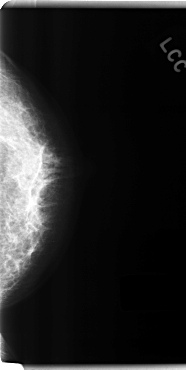

C_0198_1.LEFT_CC

LEFT_CC LINES 4800 PIXELS_PER_LINE 2408 BITS_PER_PIXEL 12 RESOLUTION 50 NON_OVERLAY